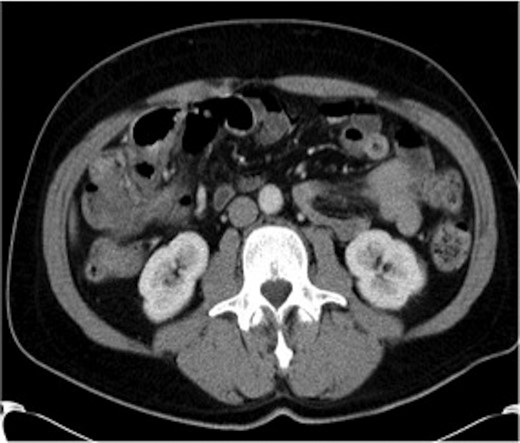

Haemoglobin was 14.9 g/dl and the white cell count (WCC) was 9 × 109/l. Other remarkable laboratory tests included a C-reactive protein (CRP) of 15 mg/l. Urinalysis was normal. The plain X-ray abdomen (AXR) (Fig. 1) revealed dilatation of a focal segment of large bowel with mildly dilated small bowel. Computed tomography (CT scan) of his abdomen reported that the gas-filled viscus is likely to represent the caecum (Fig. 2).

Plain AXR (Case 1) revealed dilatation of a focal segment of a large bowel with a mildly dilated small bowel.

CT of the abdomen (Case 1) demonstrating the gas-filled caecum.